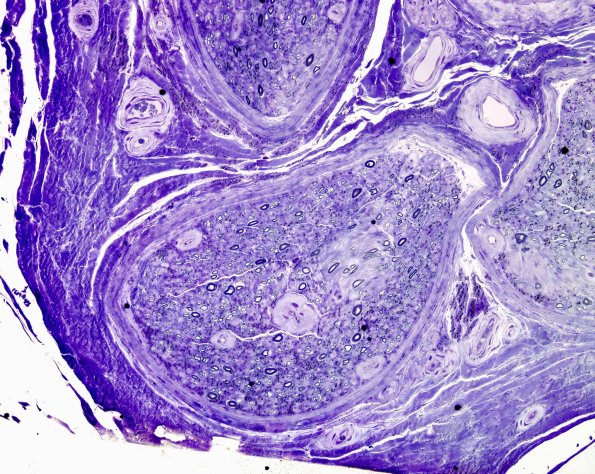

The endoneurial microvasculature is symmetrically thickened, occasionally markedly. (plastic sections. (plastic sections)